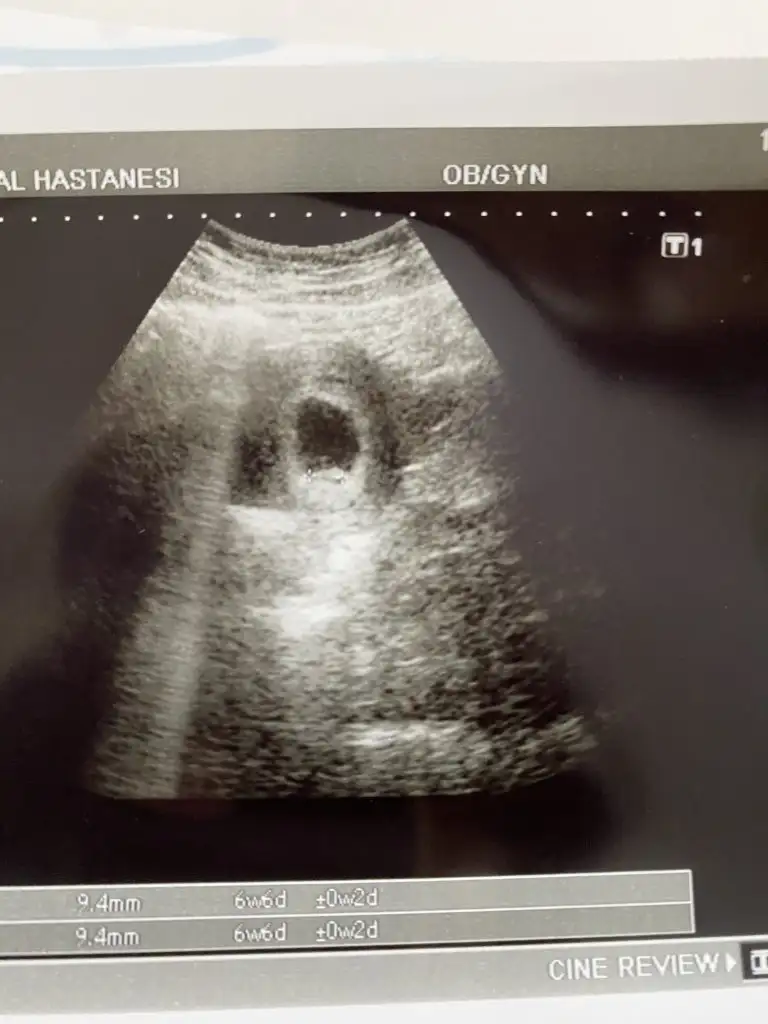

İlk ultrason resimlerinizi paylaşın ramzi teorisine göre cinsiyeti tahmin edeyim bakalım tutacak mı?

6+3 ve 8+3 karından 😌